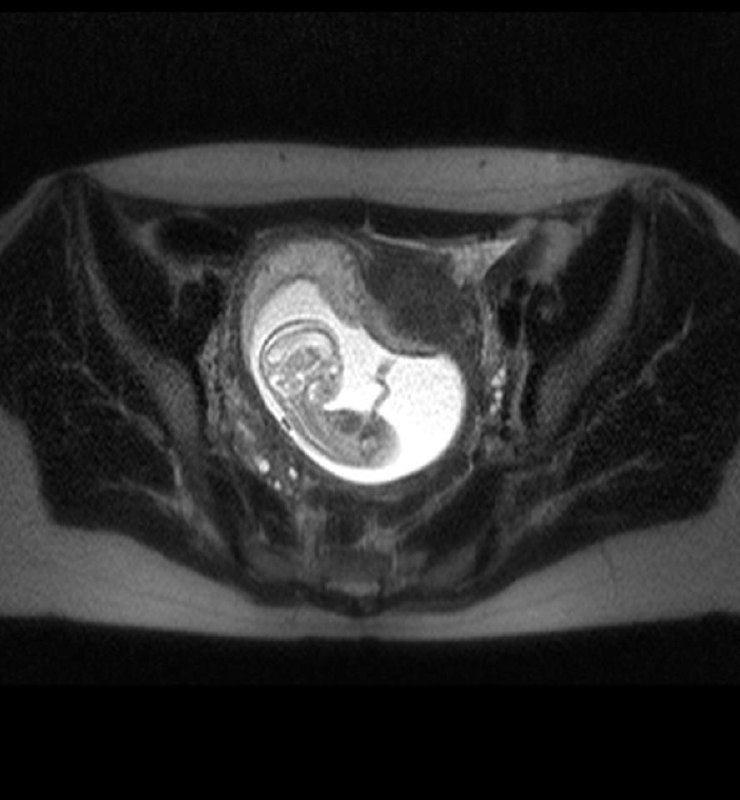

В очередной раз пополнилась наша коллекция аппендицита у беременных. Несколько дней пациентку лечили от кишечной инфекции, пока не заподозрили что-то более серьезное.

Червеобразный отросток растянут, в просвете, наряду с вязкой жидкостью, то есть, гноем, есть ещё и копролиты